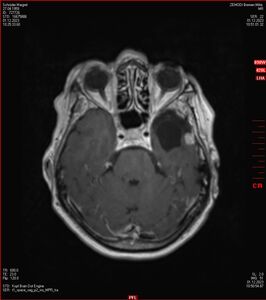

Zum Vergleich nun auch die Bilder vom 1.12.2023:

Ich denke, in den letzen 12 Monaten sind da ein paar Rezidive gewachsen,  vor 12 Monaten waren sie auch schon zu erkennen - vorher noch nicht. Nun hoffe ich auf den Rat des Spezialisten. Hoffendlich kann man etwas machen.